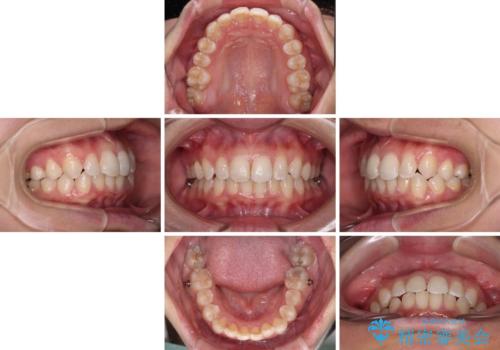

- 前歯のデコボコと歯肉に埋もれている奥歯を気にして来院された患者様です。

インビザラインでの治療を希望されていましたが、左右の下顎大臼歯が歯肉に埋もれており、特に右側は歯軸が顕著に傾斜していたため、インビザライン単独での治療は困難と判断し、ワイヤー装置を併用することとしました。

ワイヤー装置での下顎臼歯改善には時間がかかることが予想されたため、下顎のワイヤー矯正と並行して上顎をインビザラインで整え、その後インビザラインにより上下歯列を整える矯正治療を行うこととしました。

ワイヤー装置を併用したことで、レントゲン写真からも分かるとおり歯軸をしっかりと改善させることができました。